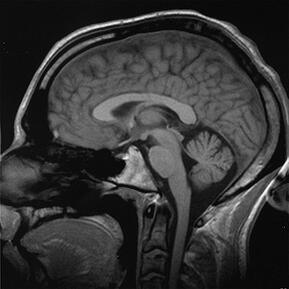

Characteristically, strokes have been known to affect mental abilities like information processing speed or attention, but not necessarily memory loss. To test the new theory, researchers conducted a study with over 650 dementia-free people aged 65 or older. The subjects were given MRI brain scans and took tests to measure their memory, language, information processing speed and visual perception. Researchers looked at the MRIs for evidence of silent strokes, which show up as dark holes indicating tissue loss. Of the 658 people tested, 174 were found to have had strokes. Those 174 performed worse on memory tests irrespective of how large their hippocampus was, though silent strokes were linked with a smaller hippocampus size.

(Photo courtesy of Wikimedia Commons)